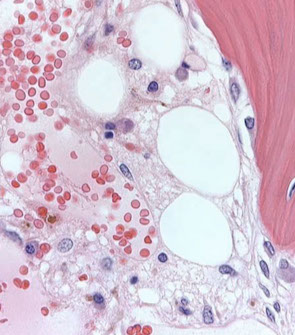

Aplastic anemia. Some eosinophilic stroma in background, very little hematopoiesis [3]

Micro:

- PB findings: pancytopenia with normal RBC morphology, macrocytosis may be present, reticulocyte index is low

- BM findings: hypocellular bone marrow, dyspoiesis, if any, is only erythroid (dysplastic neutrophils or megakaryocytes strongly suggests hypocellular MDS rather than AA)